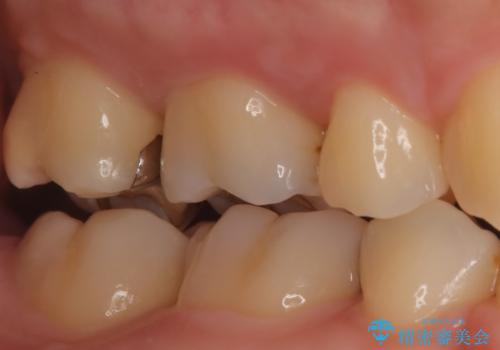

- 金属を外してセラミックを入れたいことを主訴に来院された患者さんです。

セラミックインレーにて修復を行いました。

当院でのセラミックインレーは、ラバーダムを使用して装着しております。